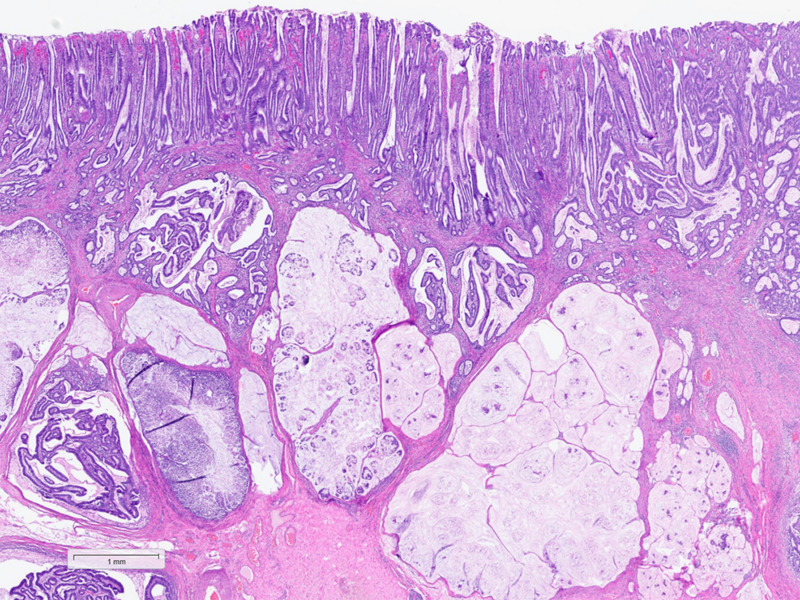

Histologically, the tumour was confirmed to be an adenocarcinoma invading through the gastric submucosa into the muscularis propria (Panel A), showing multiple architectural patterns. While the majority of the lesion displayed a tubular and papillary arrangement of neoplastic cells (Panel B), there were also mucin pools containing floating tumour cells (Panel C), as well as areas of discohesive signet-ring cells (Panel D), so called for their intracytoplasmic mucin droplet that eccentrically displaces the nucleus. The different architectural patterns were not entirely independent of each other nor were they intermingled, but rather arranged side by side (Panel E).